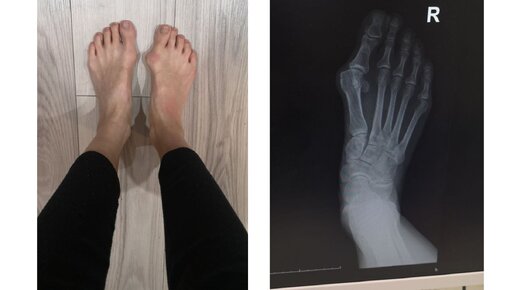

Косточка на ноге меня беспокоила давно, но с каждым годом все сильнее – большой палец отклонялся все больше и больше. Помимо косметических нюансов вальгусная деформация большого пальца доставляла и физические неудобства – было сложно подобрать обувь, плюс стопа стала сильнее болеть. С первым снегом я переобулась в привычную зимнюю обувь и поняла, что не могу ходить – все давит, больно. Начала прихрамывать. Я и раньше задумывалась об операции по коррекции Hallux Valgus, но сейчас вопрос встал ребром...